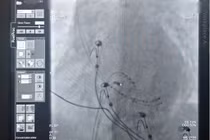

Đặc biệt, một thử nghiệm lâm sàng ngẫu nhiên mang tên DECAF công bố gần đây tại Hội nghị Khoa học tim mạch Mỹ cuối năm 2025 lại cho thấy: Ở những người vốn uống cà phê và bị rung nhĩ, nhóm tiếp tục uống trung bình khoảng một ly cà phê mỗi ngày sau khi được điều trị nhịp tim lại có tỷ lệ tái phát rung nhĩ thấp hơn so với nhóm kiêng hoàn toàn cà phê.